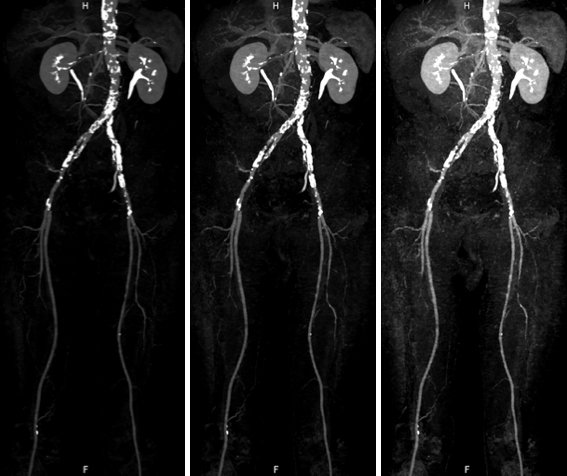

通常の画像(左:70keV)に比べ、低いエネルギーの画像では血管の描出が明瞭となっている。(中央:60keV、右:50keV)

右左両肺の下葉の肺動脈末梢に血栓性の閉塞があり(下段矢頭)、ヨードマップにて同部位の肺実質における造影剤の取り込低下が確認できます。